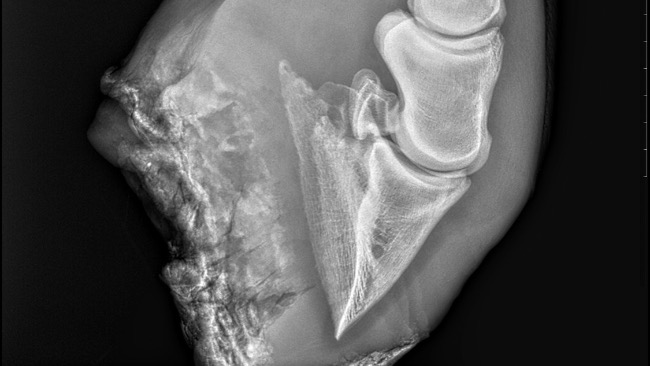

Kochani, zwracam się do Was z ogromną prośbą i nadzieją. Jakiś czas temu zadzwonił do mnie poprzedni właściciel Wichra z informacją, że nie może się nim dłużej opiekować i zapytał, czy mogłabym go przyjąć. Bez wahania się zgodziłam, chcąc dać mu kochający dom. Jednak gdy przyjechałam po Wichra, okazało się, że jego noga jest po poważnej kontuzji. Od tego momentu rozpoczęła się walka o jego zdrowie i sprawność.

Każdy, kto kocha konie, wie, jak ważne są dla nich zdrowe nogi. Bez nich tracą swoją radość, swobodę i chęć do życia. Wicher to niezwykle dzielny koń, który nie poddaje się mimo bólu, ale wiem, że bez dalszego leczenia może nie odzyskać pełnej sprawności.

Aby dać mu szansę na powrót do zdrowia, Wicher wymaga nie tylko regularnych wizyt u specjalistów, ale także specjalnych suplementów wspomagających regenerację oraz ortopedycznego podkuwania, które jest kluczowe dla jego rehabilitacji. Koszt takiego podkuwania ortopedycznego to około 500 zł co dwa miesiące. Odpowiednie suplementy to koszt około 200 zł miesięcznie, a leki to około 300 zł. Pierwsza wizyta u weterynarza kosztowała nas 400 zł, a na pewno przed nami jeszcze kilka wizyt.

Niestety, koszty tych wszystkich zabiegów, leków i terapii są ogromne i przekraczają moje możliwości finansowe. Jeżeli nie uda nam się wyprowadzić tej nogi, konieczna będzie operacja, której koszt samego cięcia ścięgna to około 5000 zł.